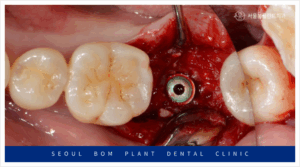

오금역치과 서울봄플란트에서는 임플란트 식립 전,

부족한 잇몸뼈를 채우기 위해

다량의 뼈이식을 먼저 진행하였습니다.

뼈이식은 임플란트를 안정적으로 식립하기 위한

필수적인 과정으로, 잇몸뼈가 부족한 경우에

필요한 치료입니다.

뼈이식 후에는 하얀색 막인 흡수성

멤브레인으로 이식한 부위를 덮어주었습니다.

이 흡수성 멤브레인은 이식한 뼈가

유실되지 않도록 단단하게 잡아주며,

뼈가 단단하게 굳는 동안

그 자리를 보호하는 중요한 역할을 합니다.

이 멤브레인은 골 형성 보조 기능을 담당하며,

차후 임플란트 식립 시 성공률을

더욱 높여주는 역할을 하게 됩니다.

뼈가 제대로 형성되기 위해서는

외부 자극이나 압력에 의한 손상을

방지해야 하므로, 이 멤브레인이

중요한 보호막 역할을 하는데요.

결국, 흡수성 멤브레인은 임플란트 식립 전후의

뼈 건강에 중요한 기여를 하며,

임플란트가 안정적으로 자리 잡을 수 있도록 돕습니다.

임플란트 식립을 위해 잇몸을 절개하여

내부를 확인해 보았더니,

뼈가 단단하게 자리 잡은 것을 확인할 수 있었습니다.

이로써, 충분히 안정적인 뼈 상태에서

임플란트를 식립할 수 있는

환경이 마련되었음을 알 수 있었습니다.